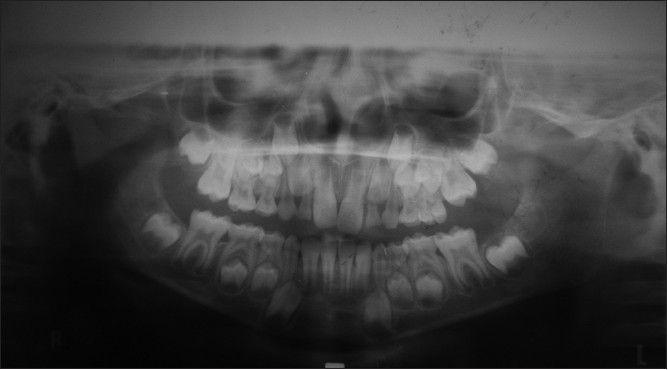

Most developing Class III patients display a retruded maxilla. Early intervention in mixed dentition is associated with better patient compliance and possibly a better orthopedic response, which can produce favorable results. The aim of this article is to present the fabrication of the new modified tandem appliance and its use in management of developing Class III malocclusion. The therapeutic results of a new modified tandem appliance are presented in an 8 year-old male patient with anterior cross bite and retrognathic maxilla at the mixed dentition stage. Anterior cross bite was corrected in 3 months and the positive overjet of 4 mm after continued use of the appliance for 1 year. There was a significant improvement in profile of the patient. The use of this appliance in this type of malocclusion enabled the correction of malocclusion in a few months and encouraging favorable skeletal growth in the future.

大多数处于生长发育期的III类患者表现出上颌后缩。在混合牙列期进行早期干预,患者的依从性更好,并且可能获得更好的矫形反应,从而产生良好的效果。本文的目的是介绍新型改良串联矫治器的制作及其在生长发育期III类错牙合畸形治疗中的应用。本文展示了一名8岁男性患者在混合牙列期使用新型改良串联矫治器治疗前牙反牙合和上颌后缩的治疗结果。3个月内前牙反牙合得到矫正,继续使用矫治器1年后覆盖达到4mm的正值。患者的侧貌有显著改善。在这类错牙合畸形中使用该矫治器,能够在几个月内矫正错牙合,并有望在未来促进有利的骨骼生长。